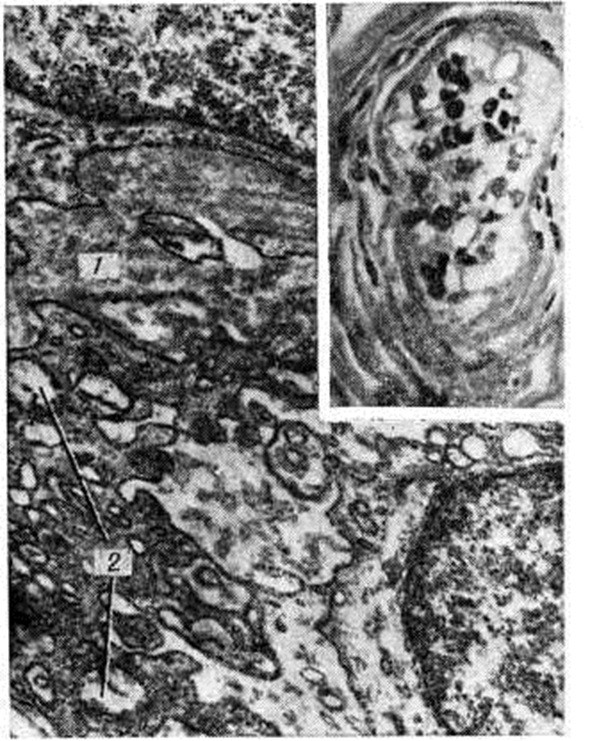

Рисунок 4.

Электронограмма кровеносного сосуда почки при артериолосклеротическом нефроциррозе: 1 — гиалин; 2 — стенка сушенной артериолы; 3 — отверстие в эндотелии; × 8000.

Рисунок 6.

Препарат микроциркуляторного русла кожи при сахарном диабете, выражен гиалиноз (биопсия). Утолщение и уплотнение базальной мембраны (1) капилляров кожи, выраженное набухание митохондрий (2); × 25 000. Вверху справа — гиалиноз артериолы кожи: пролиферированные, вакуолизированные эндотелиальные клетки (окраска гематоксилин-эозином; × 200).